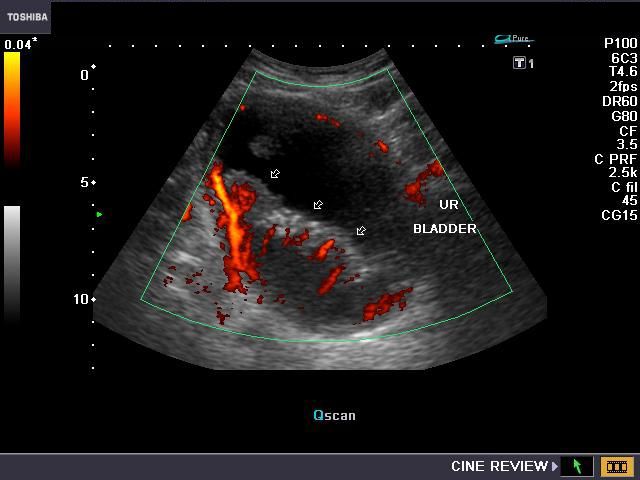

The above ultrasound images show transrectal imaging of the urinary bladder with a small left ureterocele visible. The left ureter also appears mildly dilated (hydroureter). The ureterocele is seen partially distended and also seen in the collapsing stage as the pressure builds up within the sac (of the ureterocele) with resultant evacuation of the urine into the bladder (seen on Power Doppler image- lower right). The jet of urine is seen emanating from the ureterocele sac. All 4 ultrasound images taken via TRUS study using Toshiba Nemio-XG system.